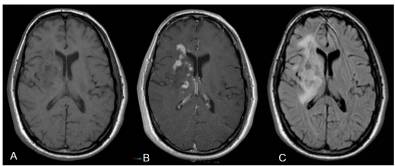

患者男性,21岁;主诉左侧肢体进行性轻偏瘫,既往无慢性病史及家族史。查体发现,左侧肢体肌力为4~5级,锥体束征阳性;未见明显颅内高压症状。术前行颅脑MRI扫描示:右侧额叶多处强化病灶,在右侧基底节区肿瘤周围和胼胝体可见明显水肿(图1)。

图1. 颅脑MRI示:A.T1相轴位片示,右侧基底节区异常信号病灶;B.T1相增强轴位片可见右侧基底节区强化病灶;C.FLAIR轴位片示,右侧基底节区高信号病变及瘤周水肿带。